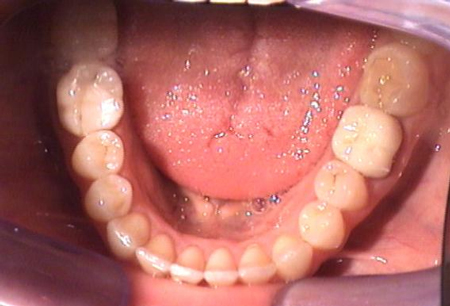

Trattamento ortodontico di una grave II Classe, paziente di sesso femminile di Età 23 anni

Trattamento ortodontico di una grave II Classe, paziente di sesso femminile di Età 23 anni.

Durata del trattamento circa due anni.

Foto finali